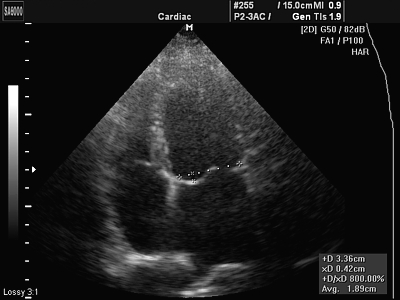

Среди обилия доступных в настоящий момент методик самой безопасной и одновременно точной считается эхокардиография сердца, которую можно сделать в любой больнице или частном медицинском центре.

Следует заметить, что исследование делается с помощью ультразвукового аппарата, соответственно эхокардиография сердца и узи сердца – это одно и то же, просто первый термин используется в основном в медицине, тогда как второй получил большее распространение среди рядовых граждан.

- с помощью датчика с особым кристаллом врач сканирует ткани и получает на экране визуальное отображение;

Эхокардиография является важным инструментом в диагностике сердечно-сосудистых заболеваний. Врачи отмечают, что правильная расшифровка результатов исследования позволяет выявить как норму, так и патологии. Нормальные показатели включают размеры камер сердца, толщину стенок и функцию клапанов. Например, размеры левого желудочка и предсердия должны находиться в определенных пределах, что свидетельствует о нормальной работе сердца. Врачи подчеркивают, что важно учитывать индивидуальные особенности пациента, такие как возраст и пол, поскольку нормы могут варьироваться. Кроме того, специалисты акцентируют внимание на том, что эхокардиография не только помогает в диагностике, но и в мониторинге состояния пациента, что особенно важно для людей с хроническими заболеваниями. Таким образом, грамотная интерпретация результатов эхокардиографии играет ключевую роль в выборе дальнейшей тактики лечения.

В результате расшифровки эхокардиографии устанавливается, соответствует ли нормам параметры миокарда, левого и правого желудочка, перикарда и клапанов. Для удобства пациентов на расшифровке указывают не только его собственные показатели, но и допустимый диапазон значений. К примеру, здоровый миокард мужчины должен весить не более 182 грамм (у женщины верхняя граница составляет 141 грамм), а ударный объем крови варьироваться в пределах от 60 до 100 миллилитров.

При эхокардиографии оцениваются различные параметры, включая размеры камер сердца, толщину стенок, функцию клапанов, а также сократимость миокарда. Важно также измерить фракцию выброса, которая показывает, насколько эффективно сердце перекачивает кровь. Эти данные помогают выявить различные сердечно-сосудистые заболевания и оценить общее состояние сердца.

Нормы эхокардиографии могут варьироваться в зависимости от возраста, пола и других факторов, но в целом для здорового человека нормальные значения включают: размеры левого желудочка в диастолу до 5.6 см, фракция выброса выше 55%, нормальная функция клапанов без регургитации. Важно, чтобы результаты интерпретировал квалифицированный специалист, который сможет учесть индивидуальные особенности пациента.